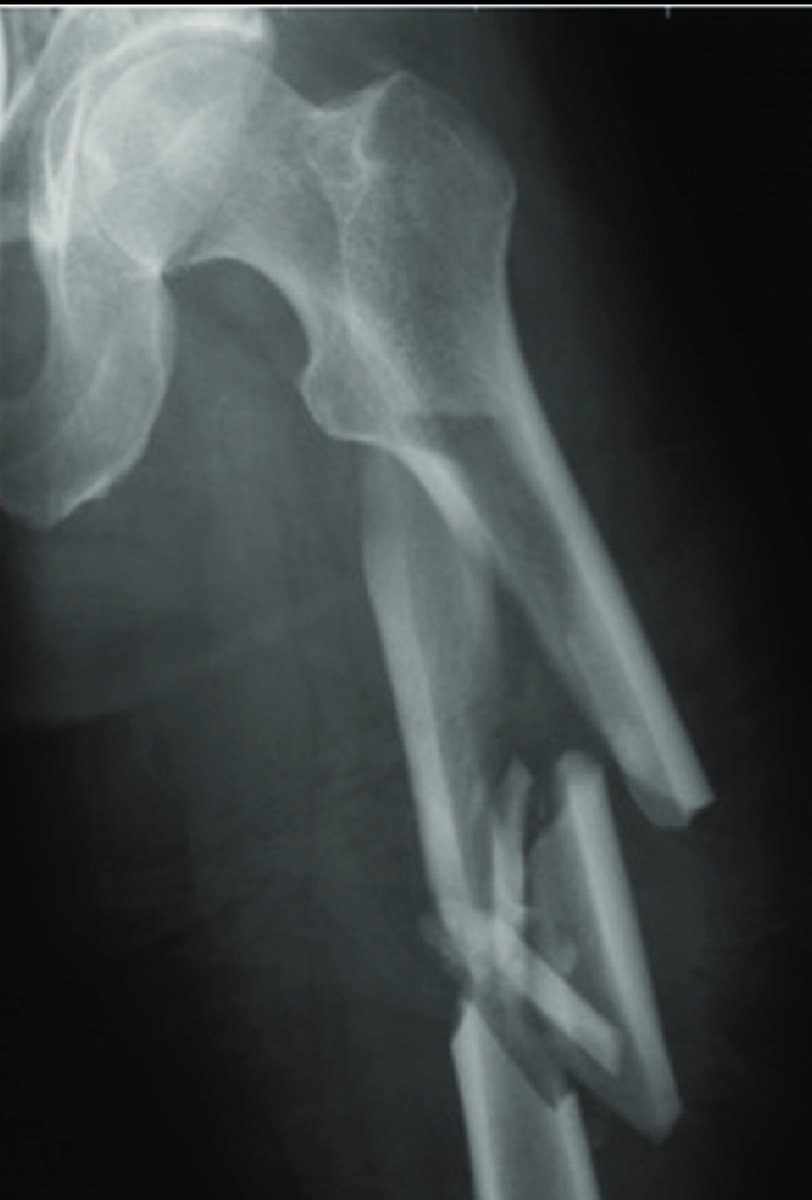

-ايضاً من العوامل طريقة علاج الكسر

هل كان جراحياً او تحفظي

حيث المبدأ الاساسي في الجراحة اعادة الطرف المكسور الى اقصى وضعية مناسبة لتساعد المريض على العودة الى الحركة واستعادة حياته الطبيعيه باسرع وقت

ومن اهم العوامل المحددة للتاهيل هي نوعية العملية الجراحية وطريقة تثبيت الكسر

فيكون القرار خلال العملية الجراحية، فالجراح على دراية كامله عن وضعية الكسر وإمكانية استعادة المشي بشكل مباشر

فنوع التثبيت المستخدم يلعب دور جوهري عن نوع التأهيل